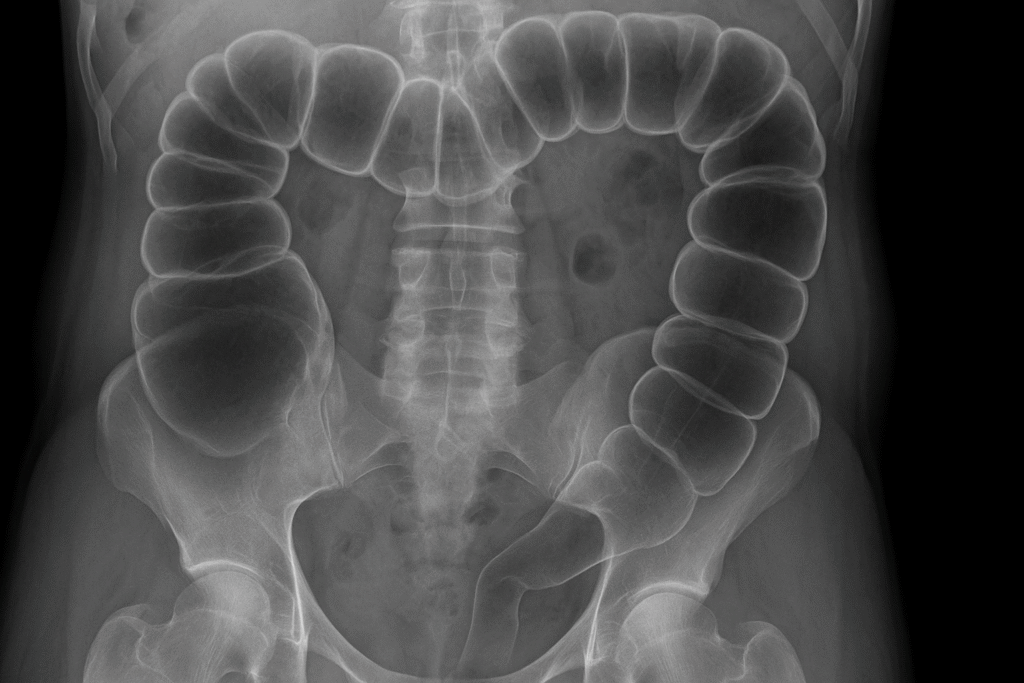

1. Plain abdominal X-ray

The humble AXR still has value:

- Peripheral dilated bowel loops (colon hugs the edges).

- Haustra visible (unlike small bowel valvulae).

- Distended caecum (>9 cm is worrying).

- Coffee-bean sign → sigmoid volvulus.